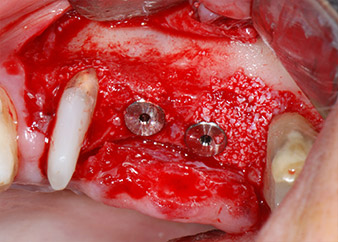

Dann wurden die Implantate (Restore, Keystone Dental) mit dem Implantatmotor eingesetzt (Abb. 11 und 12).